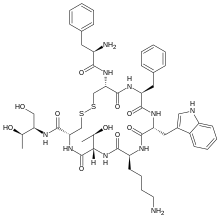

| Opioid peptides | Skeletal molecular images |

| Adrenorphin |  |

| Amidorphin |  |

| Casomorphin | |

| DADLE | |

| DAMGO |  |

| Dermorphin | |

| Endomorphin |  |

| Morphiceptin |  |

| Nociceptin |  |

| Octreotide |  |

| Opiorphin |  |

| TRIMU 5 |  |